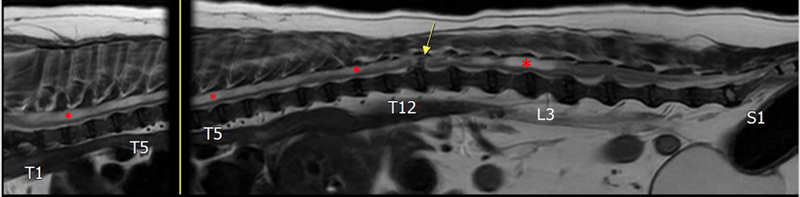

L6/7 디스크를 제외한 모든 경추 및 흉요추 디스크에서 퇴행성 탈수 소견으로 T2W 신호가 감소되어 있으며, 특히 T12/13 디스크 돌출에 의한 척수 신경 압박이 가장 두드러집니다. ▼

경추(C2–7 IVDS level)에서 퇴행성 다발성 디스크 돌출이 관찰되나, 횡단면상 유의미한 신경 압박을 보이는 부위는 없습니다.

흉단면상 T12/13 디스크 돌출은 좌측에 편향되어 척수 신경 압박하고 있으며 탈출된 디스크 물질은 Cube & T2W sequence 모두 돌출된 디스크 가장자리가 바닥보다 넓은 양상으로 관찰되어 disc extrusion (type I) 의심됨 (압박률 28%) ▼

후두부 이형성 관련한 뇌수두증 및 척수 공동증 확인되며 척수 공동증은 척수 전반에 걸쳐 광범위하게 분포하고 있습니다. 특히, C2-3, L2-3부위 grade 2 (severity of SM)로 가장 중심관 확장이 심하며 임상 증상 (통증, 민감도 변화 등) 유발 소인 높습니다.

다발성 퇴행성 경추 및 흉요추 디스크 질환 병발되어 있으며, T12/13 디스크 탈출 양상이 파열 양상으로 의심되며 돌출 부위가 좌측에 편향된 것을 고려했을 때 환자 좌측 후지 고유 자세 반응 감소는 T12/13 디스크 질환 관련성 높을 것으로 판단됩니다.

환자의 보행 실조와 후지 강직은 다발성 디스크 질환과 척수 공동증이 복합적 요인으로 생각됩니다. (추 후 척수 공동증 심화 시 운동 장애 및 근력 약화 진행될 수 있습니다.)